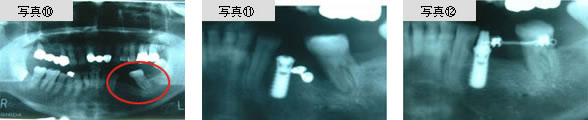

写真10は、歯の欠損を放置して隣の歯が倒れこんでしまった症例です。かつては、このような症例では抜歯するしか方法がありませんでしたが、近年はインプラントによって歯を守ることが可能になっています。写真11に示すように、植立したインプラントに矯正装置を付け、インプラントを固定源として倒れこんでいる歯を起こすことができるようになっています。たおれこんだ歯を、元の正しい位置に矯正することができるのです。

インプラントを固定源としたスプリングによって広がったスペースに、もう一本のインプラントを植立しました。(写真13参照)